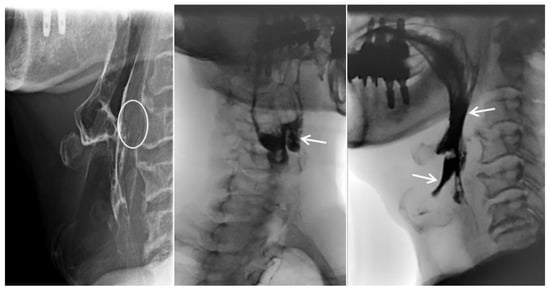

Traumatic Anterior Cervical Disc Herniation Presenting as Severe Dysphagia